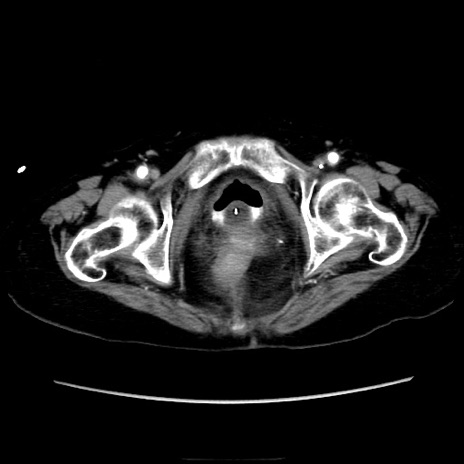

症例40(横断像)

横断像